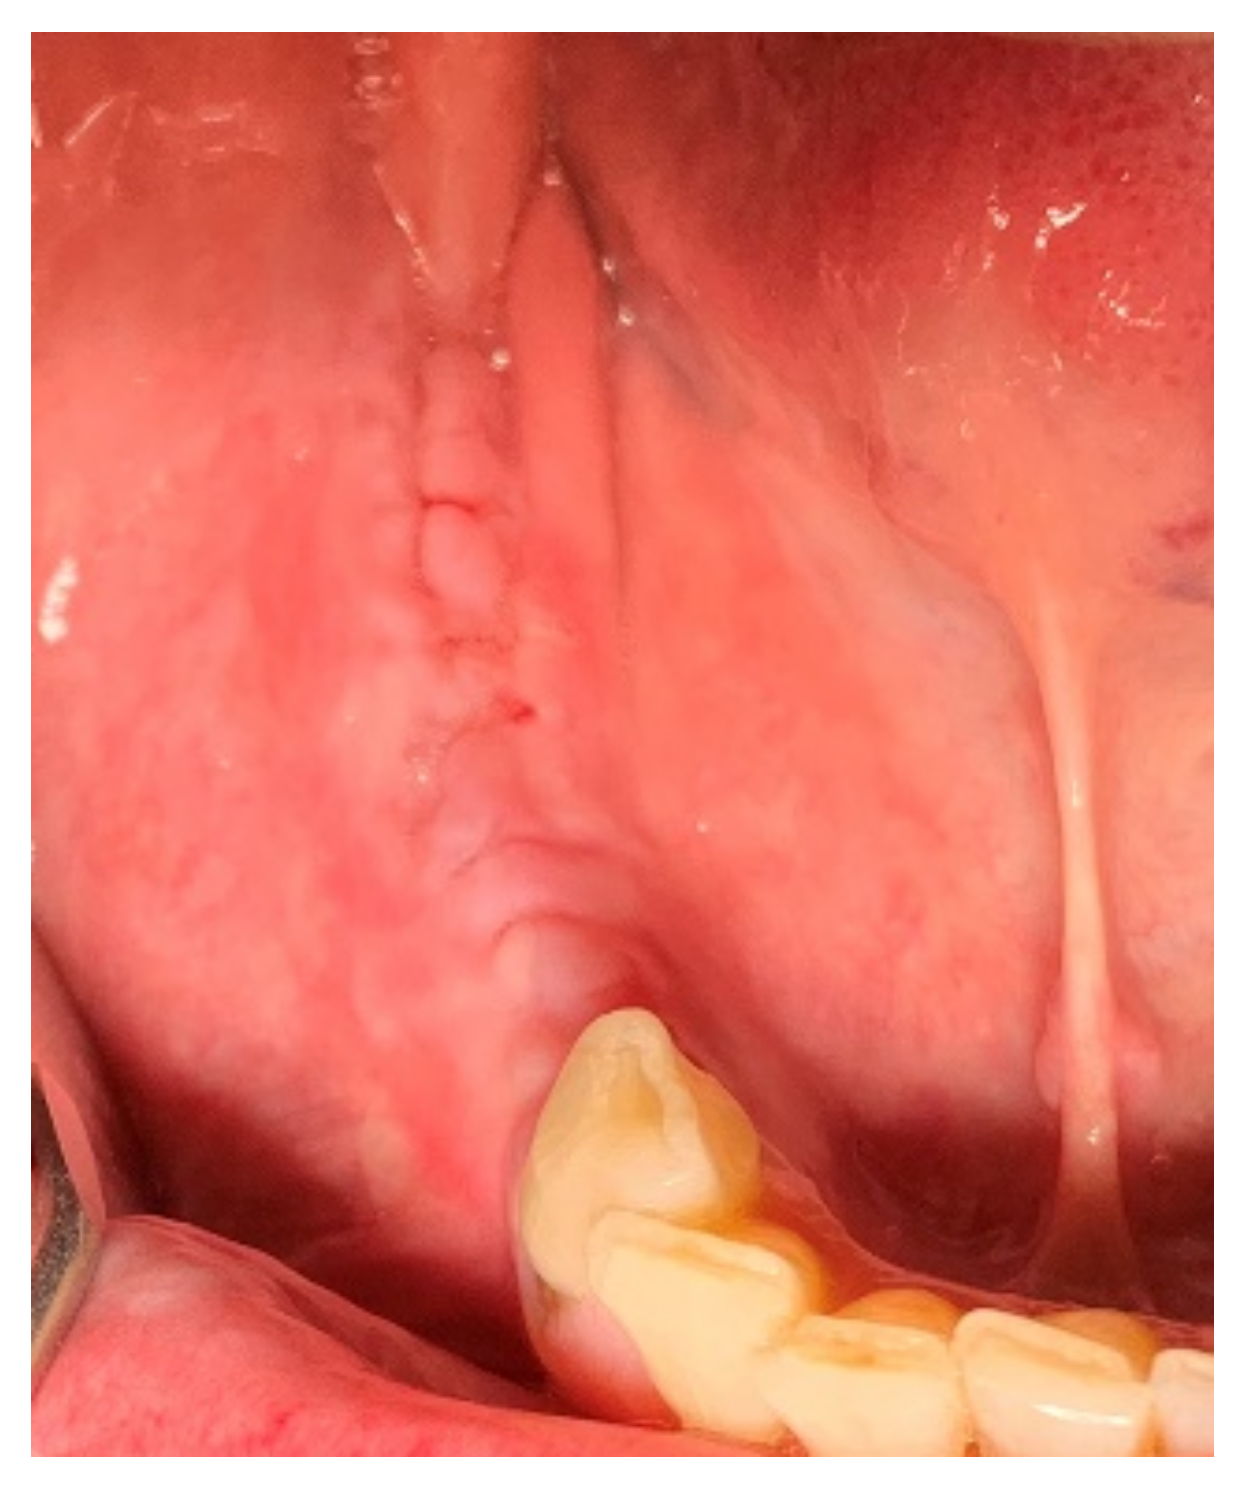

Minor swelling and slight pain were observed for the first 5 days after surgery. The sutures were removed 14 days after surgery (Figure 9). Follow-up clinical examinations were performed every 4 weeks and did not present any complications.

Figure 9.

Follow-up after two weeks.